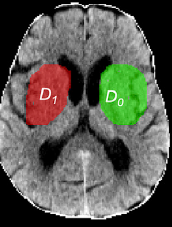

Densidade Isquêmica (Dischemic): --

Densidade Normal (Dnormal): --